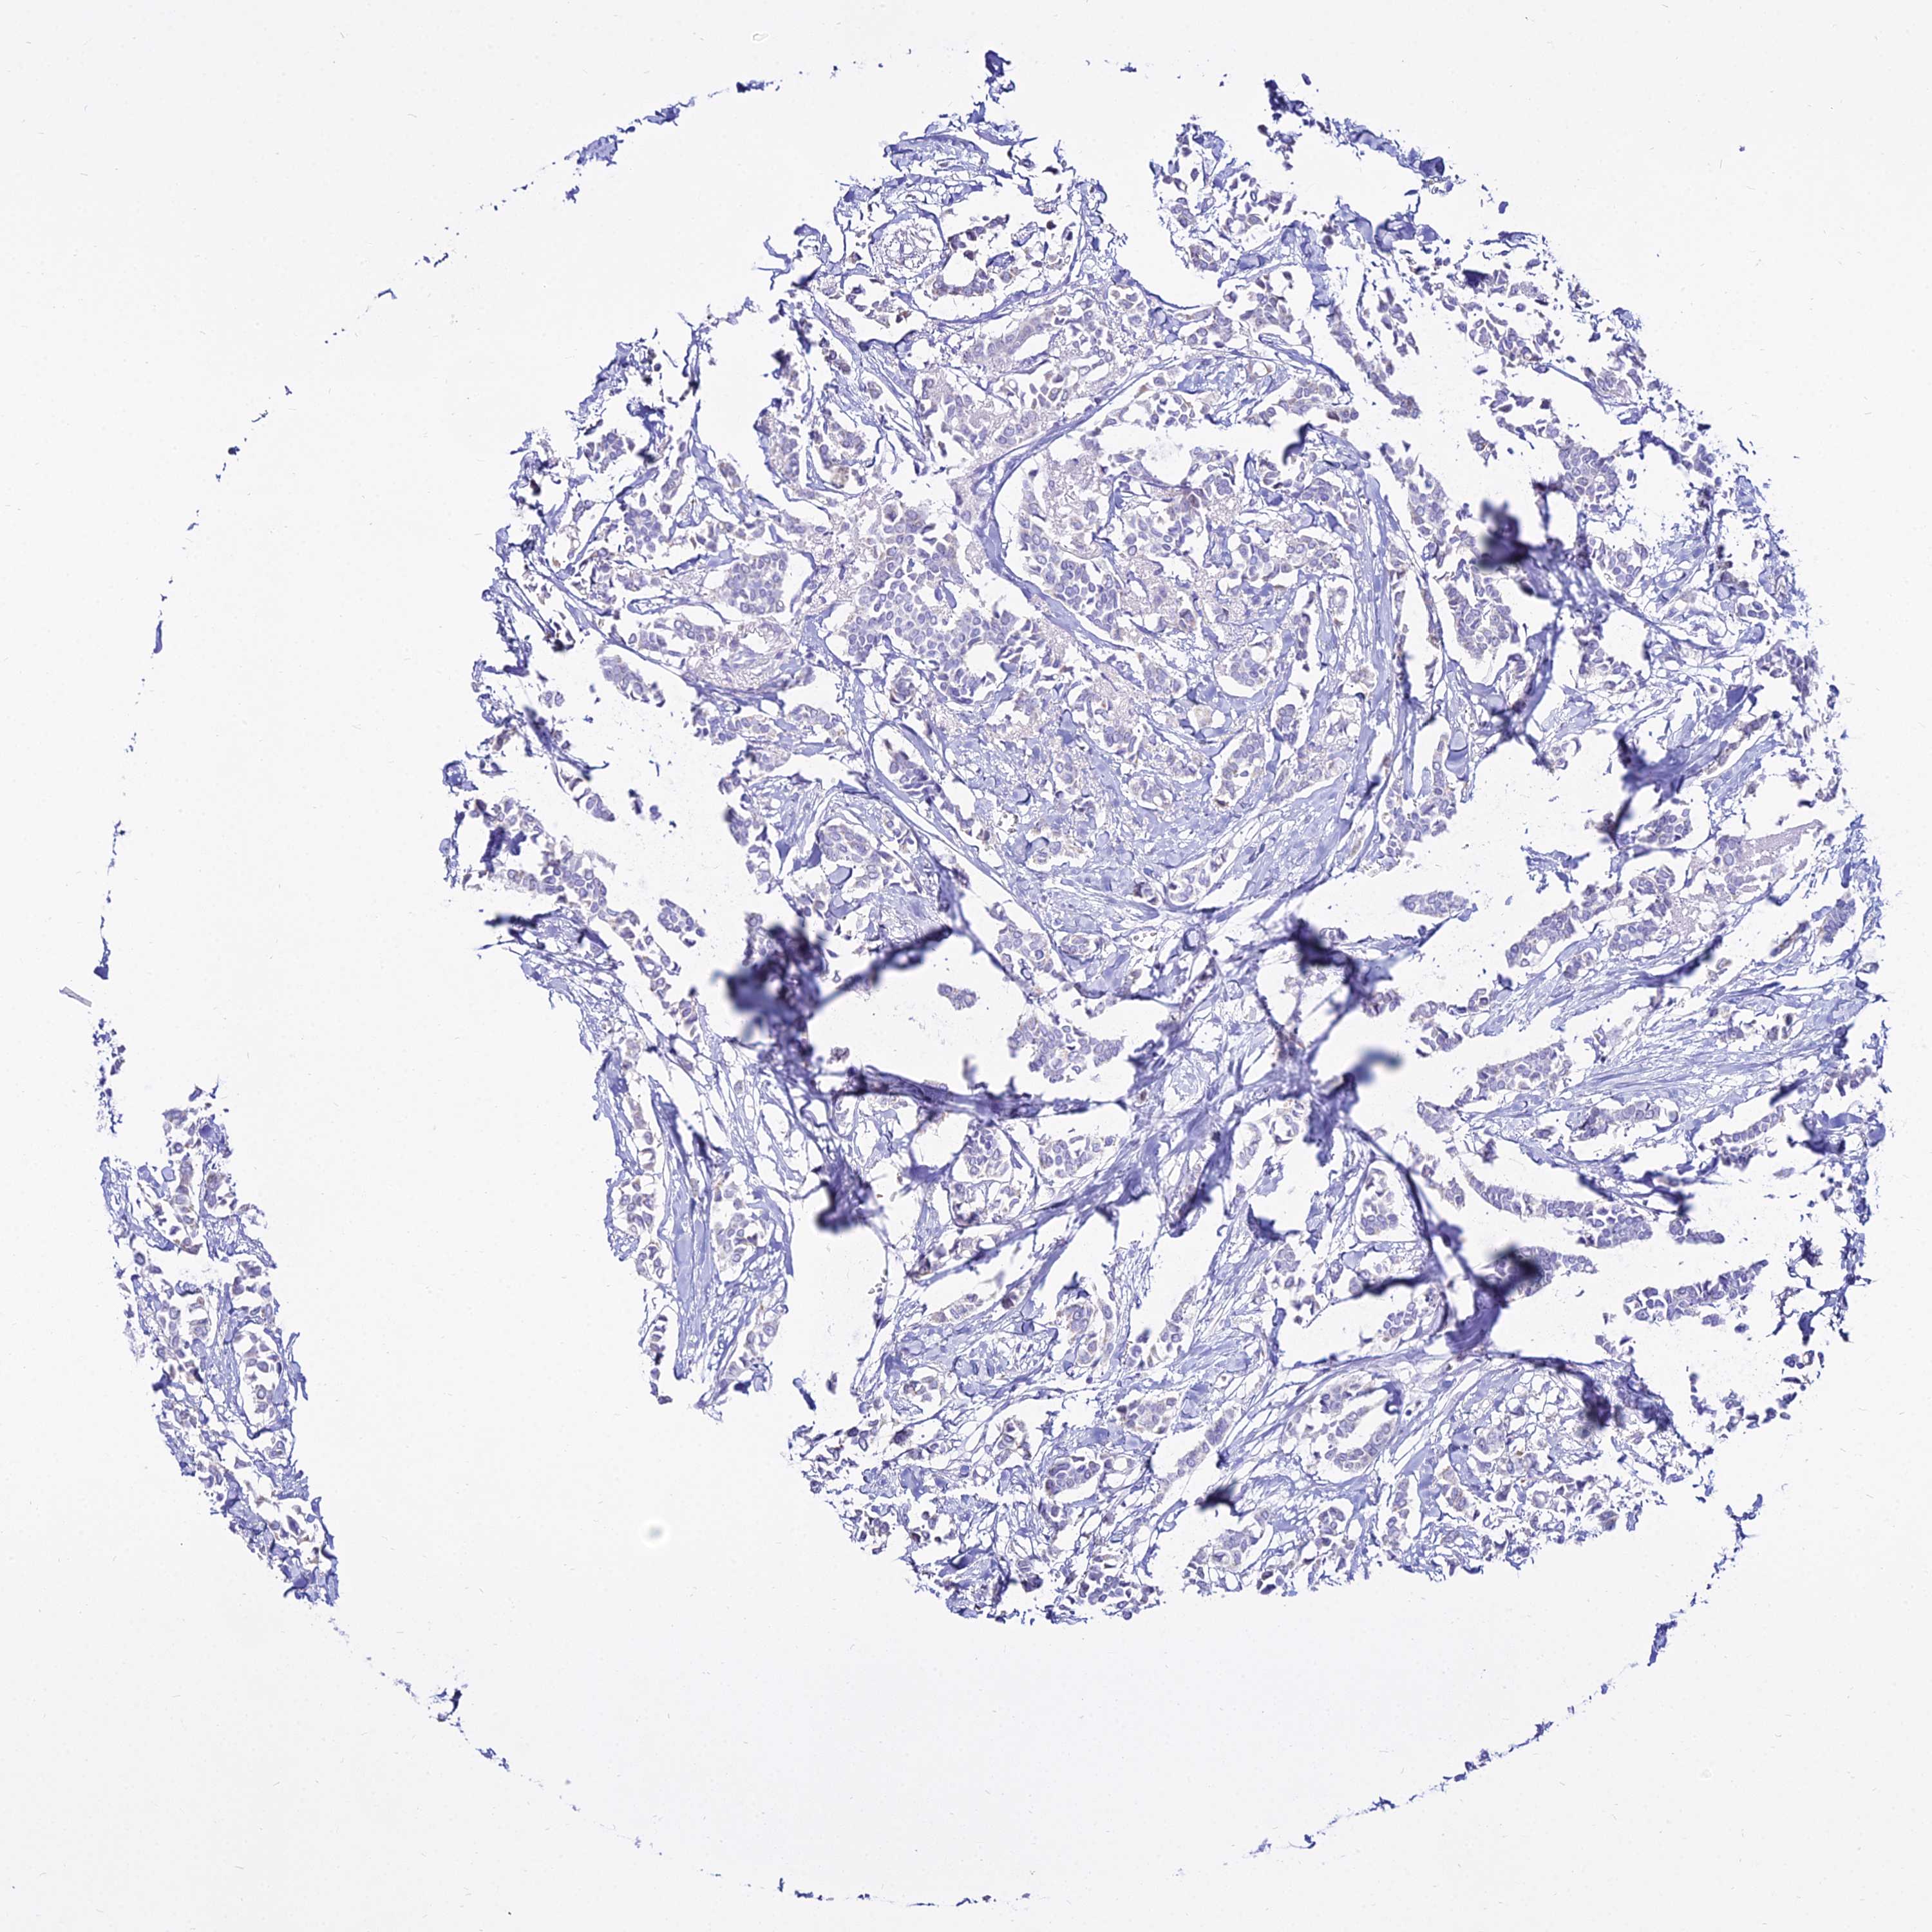

CANCER BREAST CANCER Show tissue menu

Breast cancer

Human cancer

DLX1 is not prognostic in Breast Invasive Carcinoma (TCGA)

Average pTPM 1.3

Number of samples 1022